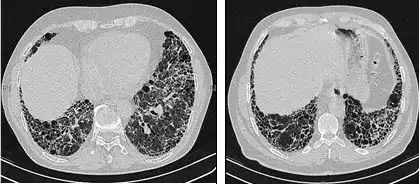

The radiological evaluation through HRCT is an essential point in the diagnostic pathway in IPF. HRCT is performed using a conventional computed axial tomographic scanner without injection of contrast agents. Evaluation slices are very thin, 1–2 mm.

Typical HRCT of the chest of IPF demonstrates fibrotic changes in both lungs, with a predilection for the bases and the periphery. According to the joint ATS/ERS/JRS/ALAT 2011 guidelines, HRCT is an essential component of the diagnostic pathway in IPF which can identify UIP by the presence of:[3]

• Reticular opacities, often associated with traction bronchiectasis

• Honeycombing manifested as cluster cystic airspaces, typically of comparable diameters (3–10 mm) but occasionally large. Usually sub-pleural and characterized by well-defined walls and disposed in at least two lines. Generally one line of cysts is not sufficient to define honeycombing

• Ground-glass opacities are common but less extensive than the reticulation

• Distribution characteristically basal and peripheral though often patchy.

High-resolution computed tomography scans of the chest of a patient with IPF. The main features are of a peripheral, predominantly basal pattern of coarse reticulation with honeycombing